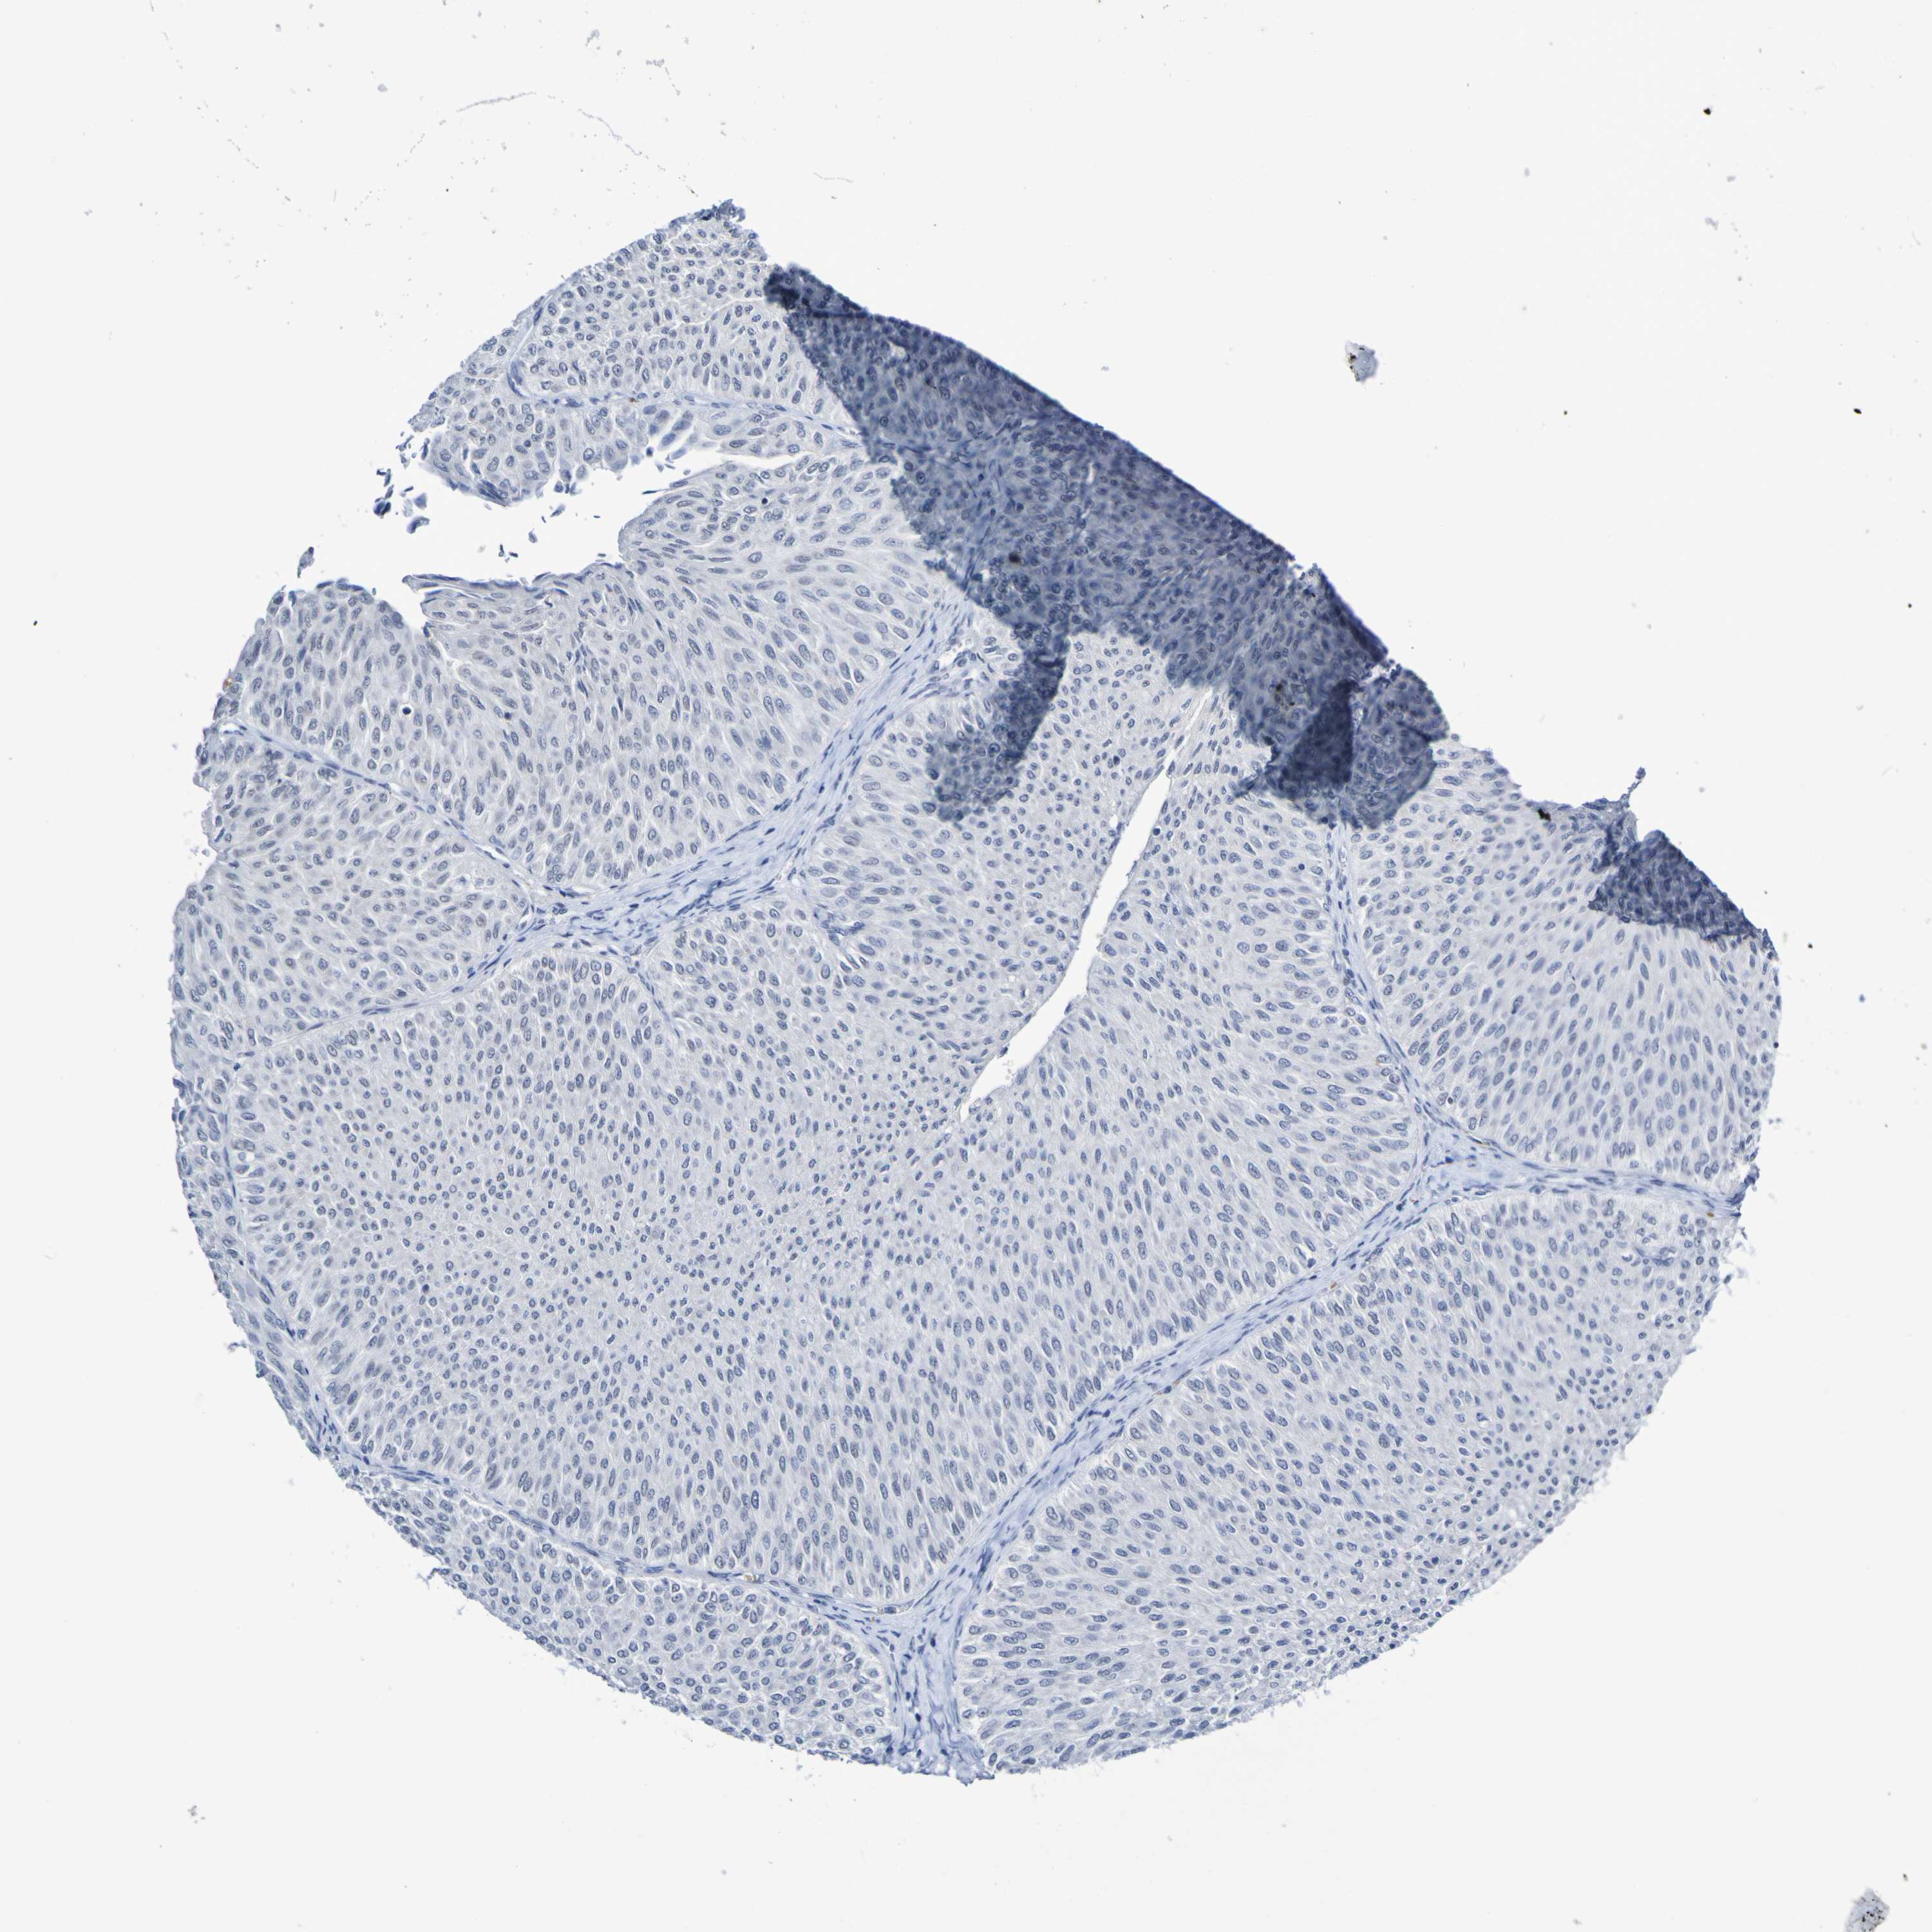

UROTHELIAL CANCER - Protein expressioni

A mouse-over function shows sample information and annotation data. Click on an image to view it in a full screen mode. Samples can be filtered based on level of antibody staining by selecting one or several of the following categories: high, medium, low and not detected. The assay and annotation is described here.

Note that samples used for immunohistochemistry by the Human Protein Atlas do not correspond to samples in the TCGA dataset.

Antibody stainingi

Antibody staining in the annotated cell types in the current human tissue is reported as not detected, low, medium, or high, based on conventional immunohistochemistry profiling in selected tissues. This score is based on the combination of the staining intensity and fraction of stained cells.

Each image is clickable and will lead to virtual microscopy that enables deeper exploration of all samples and also displays staining intensity scores, fraction scores and subcellular localization as well as patient and tissue information for each sample.

Antibody HPA011356

Staining

High

Medium

Low

Not detected

Intensity

Strong

Moderate

Weak

Negative

Quantity

>75%

75%-25%

<25%

None

Location

Nuclear

Cytoplasmic/membranous

Cytoplasmic/membranous,nuclear

Urothelial carcinoma, Low grade

Urothelial carcinoma, High grade